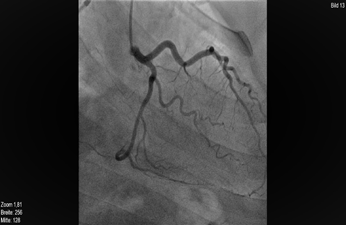

A 32 years young woman with history of hypertension, dyslipidaemia and active smoking, presented to the Emergency Department of our hospital with symptoms of unstable angina pectoris. The patient was a diagnosed case of Mid-Aortic-Syndrome with bilateral renal artery stenosis (2000) and underwent resection of the stenotic intermesenterial aortic segment with implantation of PTFE-Prosthesis and bilateral implantation of renal arteries at the very young age of 12 years. Her physical examination was unremarkable with no evidence of dyspnoea, lung congestion, murmurs or signs of raised jugular venous pulse (JVP). Her heart rate was 76 bpm and the blood pressure was stable at 130/80 mm Hg. Her daily medication was Aspirin 100 mg, Candesartan 32mg, Bisoprolol 7.5mg and Atorvastatin 40mg. An electrocardiogram (Figure 1) on admission demonstrated sinus rhythm with early repolarisation changes and laboratory analysis revealed normal blood count with normal liver and kidney functions. Initially, the cardiac biomarker (Troponin T) was 34pg/ml (normal range < 14 pg/ml) but follow up results showed a significant rise from 34pg/mL to 661 pg/mL. With the diagnosis of an acute myocardial infarction on the basis of a sudden exponential change in the Troponin levels, the patient underwent coronary angiography through the right femoral artery route (Figure 2), which revealed a disease free left main coronary artery. We were unable to identify the RCA ostium, for which an Aortography was performed and it revealed the RCA originating from left coronary sinus. Further confirmation of the anomality was done through a coronary computed tomography angiography (Figure 3). The coronary computed tomography angiography (CCTA) showed the anomalous origin of a hypoplastic RCA from left coronary sinus ventral to the left main origin, lying between the aorta and the pulmonary trunk with a negative Agatston score. The transthoracic echocardiogram revealed a normal left ventricular function without any regional wall motion abnormalities, diastolic dysfunction Grade II and minimal mitral- and tricuspid-regurgitation. Laboratory investigation for cardiotropic virus marker revealed increased values of IgG-EBV, which most probably reflects an old Epstein-Barr virus (EBV) Infection.

Figure 2 Coronarangiography.